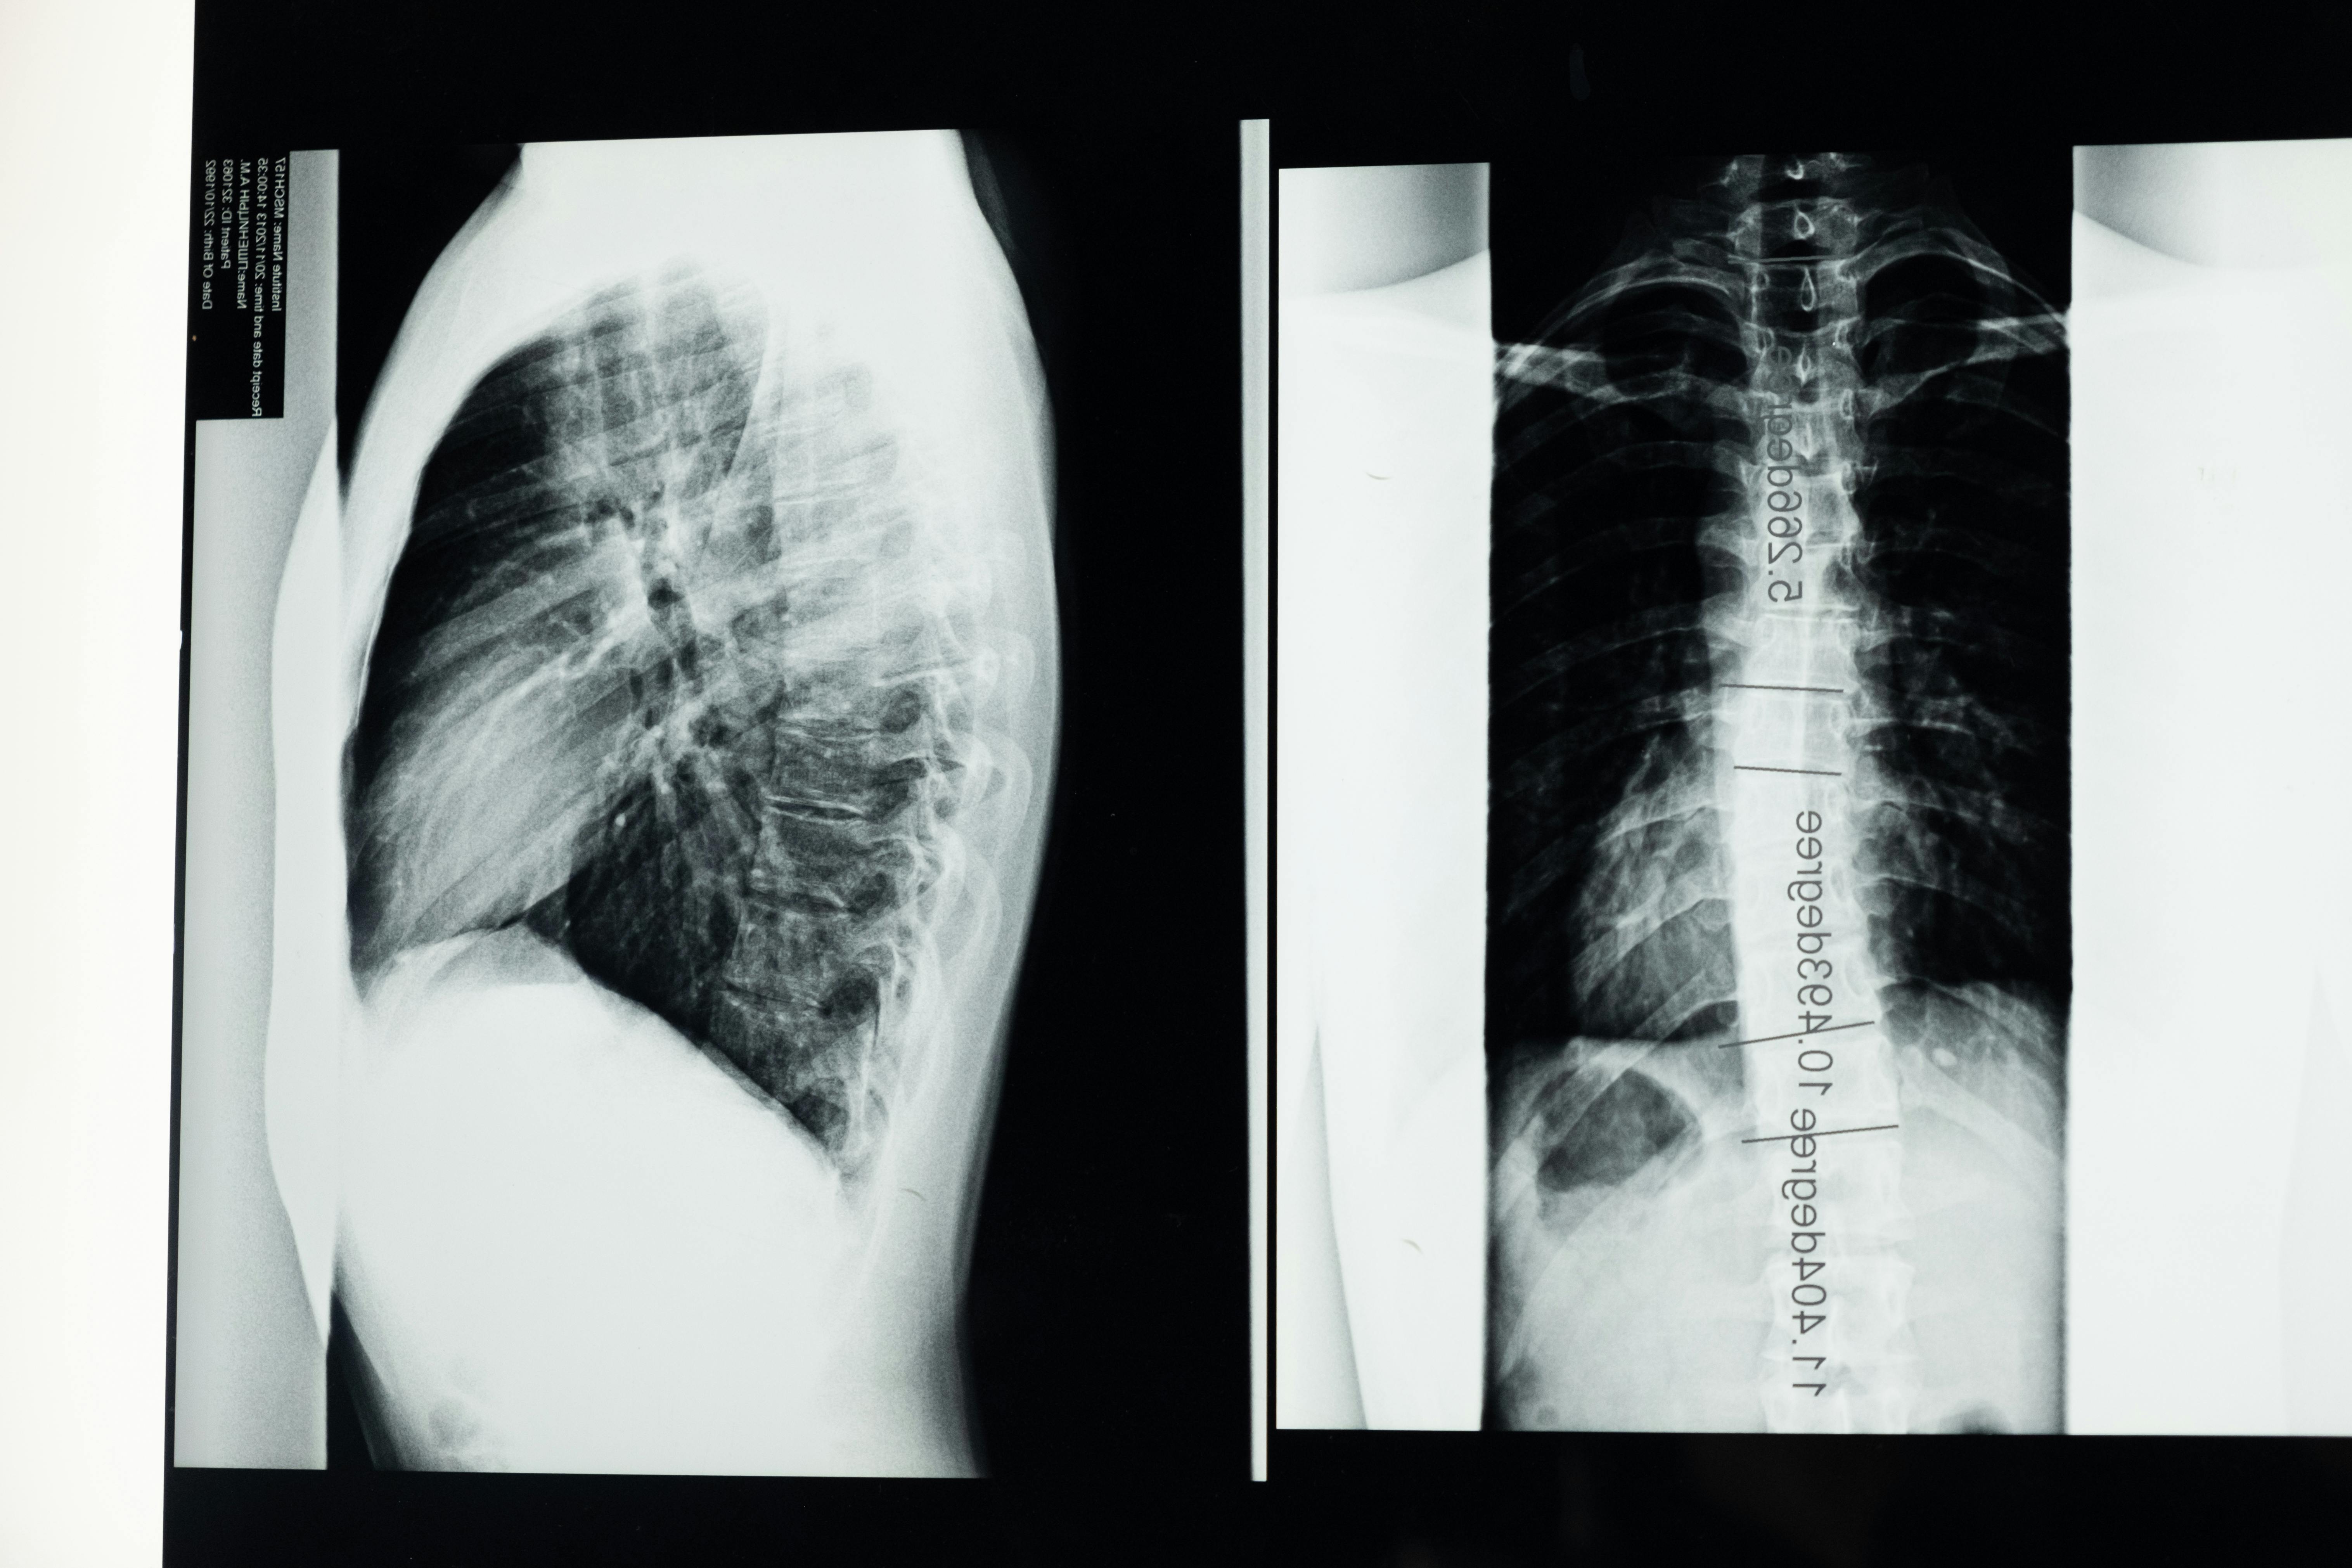

허리뼈에서 전면으로 볼록한 커브는 정상적이며 중립적인 자세이다. 한 연구는 14~15세 사춘기를 대상으로 시상한 면에서 척추의 척추뼈 몸통들을 추정하여, 척추 중앙점 커브로부터 허리뼈 커브를 계산했다. 사춘기 남성은 25.6。의 커브, 여자는 30.8。의 커브를 가지고 있다. 척추뼈 몸통에 위치한 척추중앙점

들로부터 계산된 곡선은 극돌기들과 같은 외적 표식(landmark)으로부터 관찰된

것과는 다를 것으로 기대된다. 경사계 나 유연성 테스트는 외적 허리뼈 커브를 측정하는 데 사용된다.

이들 도구에 의해 얻은 커브를 계산하기 위해 사용되는 두 가지 다른 방법 때문에 보고되는 값들에는 약간에 차이가 있다. 일반적으로 젊은 사람에서 허리뼈 커브는 25~30。고 가정된다 Ohlen과 동료들은 측정 도구로 경사계를 사용하여 연구를 한 결과 그들의 연구에서 등뼈의 커브는 30~33。 그는 40세 이하의 사람에게서는 유사한 값인 32~37。이었고, 60세 이상에서는 40~45도라고 보고하였다.

시상 면에서 후천적인 손상은 허리뼈 커브가 감소한 편 평등과 허리뼈의 커브가 증가한 앞굽음증이다.